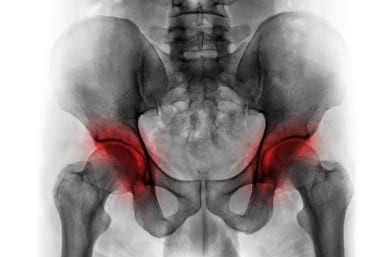

골반괴사는 정식 명칭이 '대퇴골두 무혈성 괴사'로, 다리와 골반을 연결하는 부위가 혈액 공급을 받지 못해 뼈조직이 죽어가는 질환입니다. 이 병을 조기에 진단하고 치료하지 않으면 심한 고통과 운동 제한이 따라오기 때문에 꼭 알아두어야 합니다. 특히 걸을 때 고관절에 극심한 통증을 느낀다면 즉시 주의를 기울여야 합니다. 또한 이 질환은 알려지지 않은 원인으로 발생할 수도 있지만, 음주, 스테로이드 남용, 외상 등이 주요 원인이 되고 있습니다.

골반 괴사(대퇴골두 무혈성 괴사)는 대퇴골의 머리 부분으로 가는 혈액 공급이 부족해져 뼈조직이 죽는 질환입니다. 이로 인해 대퇴골두가 붕괴되고, 결국 고관절의 기능이 저하됩니다. 주요 원인과 증상을 정리하면 다음과 같습니다.

● X-ray(엑스레이)ㅡ 대퇴골두의 모양 변형, 관절 공간의 변화, 뼈 붕괴 여부 등을 확인하는 데 사용됩니다. 하지만 초기 단계에서는 X-ray 상에서 이상 소견이 나타나지 않을 수 있습니다.